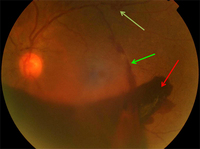

Proliferative diabetic retinopathy: new vessels elsewhere (white arrow), vitreous (intra-gel) haemorrhage (green arrow), retrohyaloid haemorrhage (red arrow)

Courtesy of Moorfields Photographic Archive; used with permission